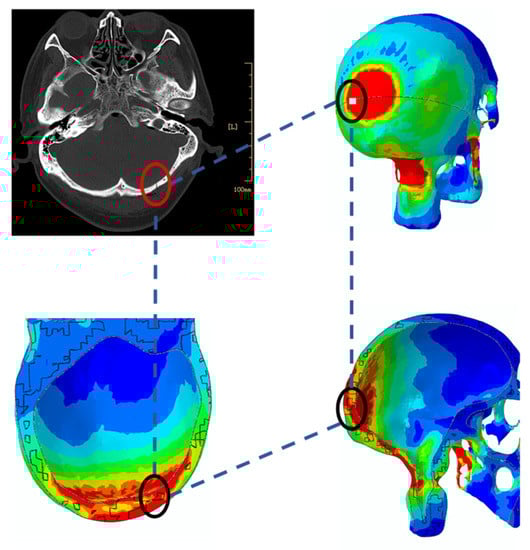

3.1. Skull Injury under Different Impact Conditions

3.2. Effects of Impact Angle on Peak Stress Value of the Skull

4. Validation